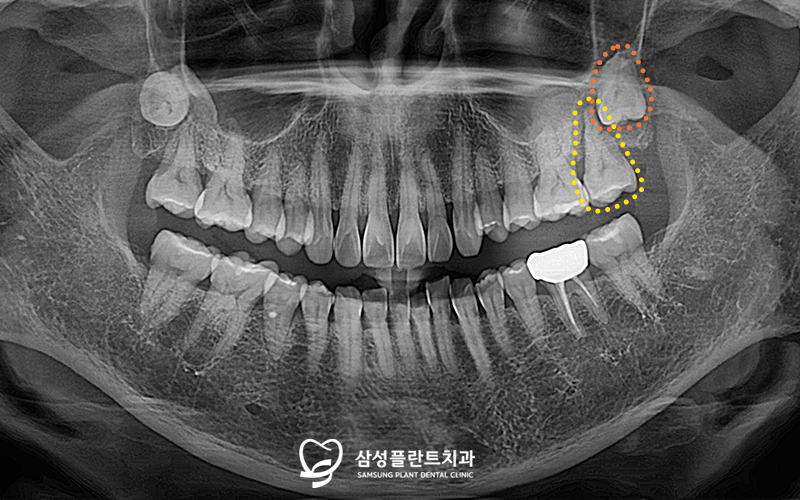

파노라마 사진을 촬영해 체크해보니

불편을 호소하는

노란색 표시의 어금니는

잇몸뼈가 녹고 염증소견도 관찰되었습니다.

또한 매복된 사랑니(주황색 표시)도

확인할 수 있었답니다.

더욱 정밀한 체크를 위해

3D-CT 촬영을 통한 정밀 분석도 시행하였고,

사랑니 발치와 함께

환자분께서 불편을 느끼고 있는 치아는

발치 후 임플란트 식립을

진행하기로 계획했습니다.

그리고 향후 임플란트를

식립해야 할 부위의

뼈 양이 부족한 상태라

발치 후 뼈이식을 먼저 진행하기로 했답니다.